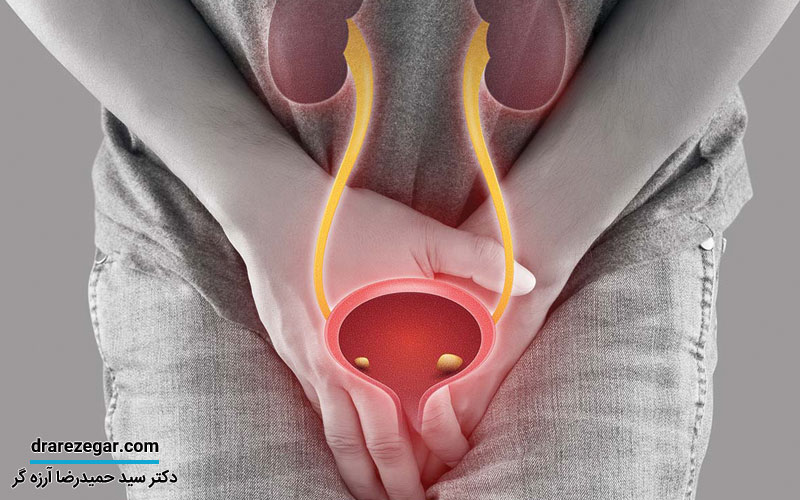

به شرایطی که در آن، لوله هدایت کننده ادرار از مثانه به بیرون یا همان مجرای ادراری ملتهب و متورم شده باشد، اورتریت گفته می شود. مهم ترین علت التهاب مجرای ادراری، ایجاد عفونت در این محل عنوان می شود. برخی از عفونت ها به تنهایی خطرناک نیستند و به خودی خود رفع می شوند. برخی دیگر می توانند خطرناک باشند و علاوه بر بروز علائم آزار دهنده، احتمال عفونت به سایر بخش های دستگاه ادراری بیشتر می شود. عفونت ناشی از عفونت مجرای ادراری می تواند به کلیه ها منتقل شوند و باعث نارسایی کلیه یا سایر بیماری های کلیوی شود. اورتریت یا همان التهاب مجرای ادراری در هر دو گروه جنسی ایجاد می شود که در احتمال بروز آن در زنان بیشتر از مردان است.

ملتهب شدن مجرای ادراری می تواند علائم مختلفی به همراه داشته باشد. به طوری که این علائم در تمامی بیماران یکسان نخواهد بود. از طرفی، نشانه های التهاب خفیف در مجرای ادراری متفاوت تر از نشانه های التهاب شدید هستند. در حالت کلی، این علائم عبارتند از:

• احساس درد، سوزش و داشتن مشکل به هنگام ادرار کردن

• تکرر ادرار و افزایش دفعات تخلیه ادرار در مدت زمان های کوتاه

• ایجاد ترشحات از ناحیه تناسلی

• داشتن یک رابطه جنسی دردناک

• احساس خارش در ناحیه مقعد

• نیاز مکرر به تخلیه مدفوع

ملتهب شدن مجرای ادراری در زنان علائم ویژه ای دارد که عبارتند از:

• احساس خارس در واژن

• ترشحات غیر عادی از واژن

• خونریزی های غیر طبیعی در بین دو دوره قاعدگی

• داشتن تب و لرز

• متورم شدن ناحیه واژن

• احساس درد ناحیه زیر شکم و لگن

• تجربه خونریزی های شدید در دوران قاعدگی